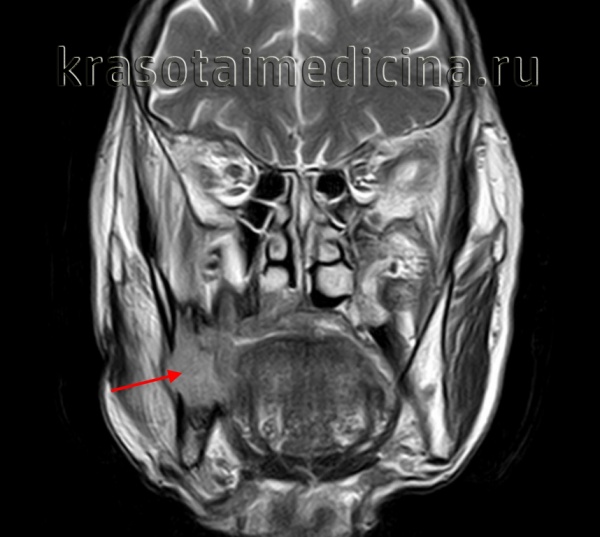

(Слева) МРТ Т1ВИ с КУ, коронарная проекция, этот же пациент. По нижнечелюстному нерву опухоль распространяется в овальное отверстие и тройничную полость. Также опухоль прорастает латеральнее, в твердую мозговую оболочку средней черепной ямки.